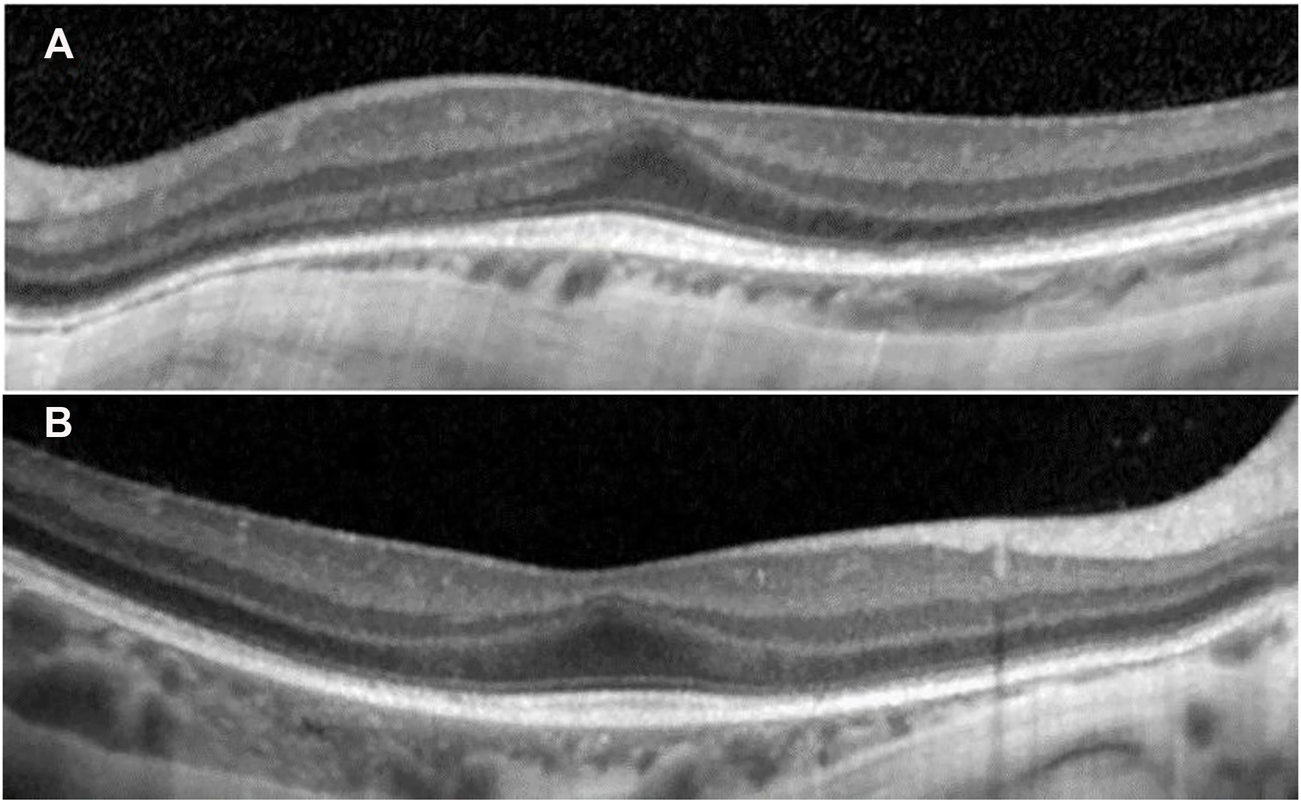

Ophthalmologic evaluation at the age of 4 y led to the diagnosis palpebral ptosis, descending palpebral fissures, high myopia, astigmatism, retinal dystrophy, and pigment deposits in the retina. At age 8 y, he had similar ophthalmologic findings, however with advanced myopia. The best corrected visual acuity at distance using the logMAR VA chart was 0.5 logMAR for the right eye (RE) and 0.3 logMAR for the left eye (LE). For each cycloplegic refraction, a conversion to the spherical equivalent was made (−11.5 diopters for the RE, −12.75 diopters for the LE). His axial length (measured with a Topcon Aladdin Optical Biometer) was 27.39 mm in the RE and 27.33 mm in the LE, respectively. Average axial length for age and gender was 23.31+/−0.48 mm (Tideman et al., 2018). The diopters and increased axial length demonstrated the diagnosis of high myopia. Indirect ophthalmoscopy (with dilated pupil) showed peripapillary chorioretinal atrophy, increased visibility of the choroidal vasculature, optic disc with oval appearance, and macular and peripheral retinal pigment epithelial changes. The color vision was normal (Ishihara’s color plates). Electroretinography (ERG) examinations were performed according to the International Society for Clinical Electrophysiology of Vision standards (after 20 min of adaptation to darkness and 10 min of adaptation to light) using skin electrodes. Full-field ERG recorded a decreased functionality of the rods and the cones in the entire retina of both eyes, confirming the diagnosis of rod-cone dystrophy in both eyes. The visual-evoked potential test revealed increased P wave latency, showing damage to the myelin sheath of both optic nerves. Spectral domain optical coherence tomography was performed with pupils previously dilated (Spectralis OCT, Heidelberg Engineering, Germany). A single-line scan protocol was used for a horizontal cross section through the fovea (ART 100 frames). SD-OCT images from horizontal cross section through the retina showed foveal hypoplasia, conservation of inner retinal layers, and alterations of the external layers and choroidal thinning at the nasal extremity (Figure 2).

SD-OCT images from horizontal cross section through the retina showed in both eyes (A) left eye and (B) right eye: increased central foveal thickness (CFT was 251 μm for the left eye and 250 μm for the right eye), absence of the foveal depression, preservation of the inner retinal layers in the fovea (foveal hypoplasia), intact ellipsoid zone (EZ) in the fovea, disruption areas in the external limiting membrane (ELM), decreased outer nuclear layer (ONL) thickness, and weak delimitation of outer segments of photoreceptors and choroidal thinning at the nasal extremity in the retinal pigment epithelium (RPE).

A possible retinal phenotype (retinal dystrophy, myopia, and astigmatism) was reported in relation to DNAJC21 in several other people (Tummala et al., 2016; Dhanraj et al., 2017; D’Amours et al., 2018). This report provides a detailed eye phenotype, showing high myopia, rod–cone retinal dystrophy, altered myelination in the optic nerves, and changes in the retinal layers with foveal hypoplasia, conservation of inner retinal layers, alterations of the external layers, and choroidal thinning at the nasal extremity.